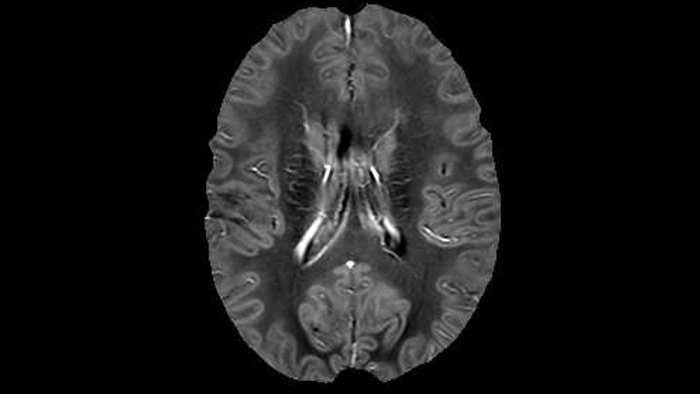

Sagittal 3D FLAIR with 0.3 mm3 voxel volume acquired in 5:12 min. using Compressed SENSE showing a (juxta)cortical MS lesion.

He says the accelerated scanning is achieved via the use of Compressed SENSE and MultiBand SENSE. “We can use Compressed SENSE acceleration factors of about 10 on a 3D FLAIR for instance, which is quite remarkable compared with what we saw with the Achieva. With 3D FLAIR, we can push the spatial resolution to 0.3 cubic mm and it works. Previously, our 3D FLAIR scans lasted about 8 minutes, but now with Elition they are five minutes. The SNR is also visibly better. Our SWI and QSM scans look fantastic. Also, since a lot of neuroimaging is EPI based, using the MultiBand SENSE technique can increase temporal resolution and make it possible to run complicated DTI scans relatively quickly.”

“In addition to traditional imaging like FLAIR for lesion identification, we see a real push towards techniques that weren’t normally required for MS, including good highresolution 3D T1 weighted images to do volumetrics. We’ve also started looking at spinal cord imaging again, since techniques have improved in terms of acquisition and analysis. Another important technique is susceptibility weighted imaging (SWI), particularly if we are looking for central veins in lesions, which is extremely helpful for diagnosis.”